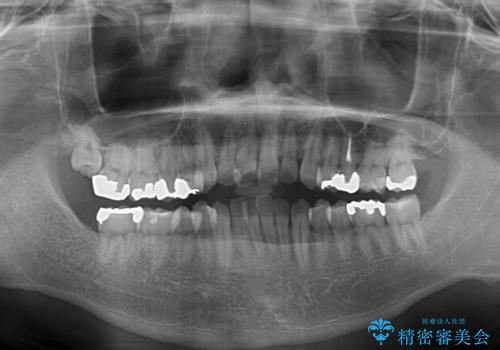

- 前歯のデコボコとクロスバイトを気にして来院された患者様です。

インビザラインによる前歯のクロスバイト改善におけるリスクとして、前歯歯髄充血・歯髄壊死が挙げられます。

ワイヤー矯正を併用する目的として、短期間でデコボコやクロスバイトを改善する他に、歯髄充血リスクを低減させるというものがあります。